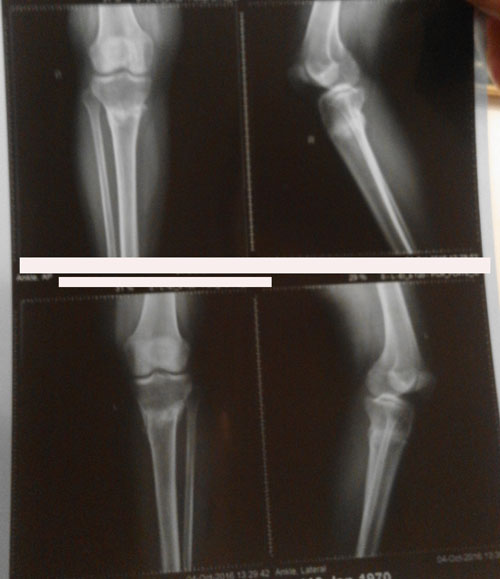

Рентген в 60 дней.